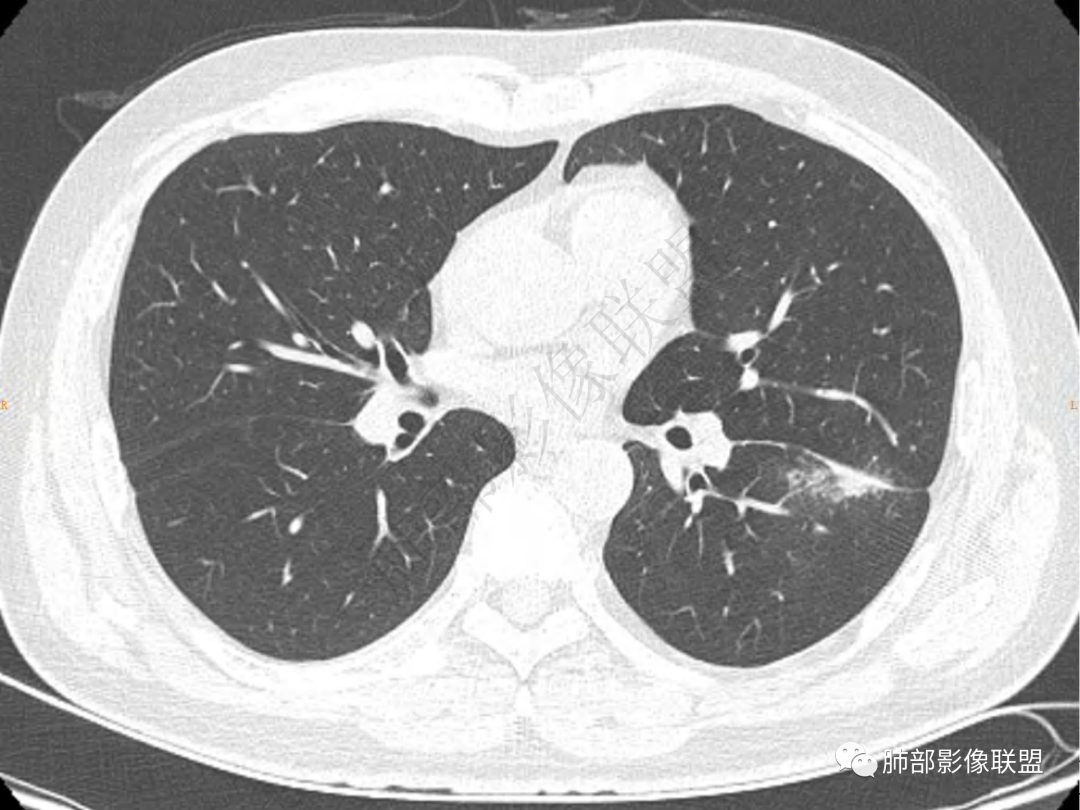

1.中年男性,咳嗽咳痰20余天,间断咯血2周

2.左肺下叶团片影,跨背段及内前基底段,实性部分类椭圆形,密度不甚均匀,可见毛刺及棘状突起,未见典型分叶及胸膜凹陷。病灶上下缘可见相应肺段支气管旁进侧出,管壁轻度增厚,未见狭窄阻塞。

3.周边较大范围磨玻璃影,边界相当模糊,小叶增厚明显。注意叶裂另一侧、左肺舌段亦可见磨玻璃影及增厚的小叶间隔。未见明确卫星病灶。

4.实性部分不均匀环形强化并显示一小范围低密度坏死区或空洞。较之肺窗,整体纵隔窗范围较小,提示病灶并不十分密实。抑或为不同时段图像。

5.双肺门及纵隔未见增大淋巴结。未见胸腔积液。

1.病灶不够密实,没有典型分叶,收缩乏力等,支气管未见截断等,缺乏一般肿瘤性肿块特征。

2.周围磨玻璃影边界不清缺乏限制,甚至“激惹”到相邻肺叶,也许提示较明显的炎性水肿。

正如多数老师分析到的,本例病灶炎性特点比较明显。